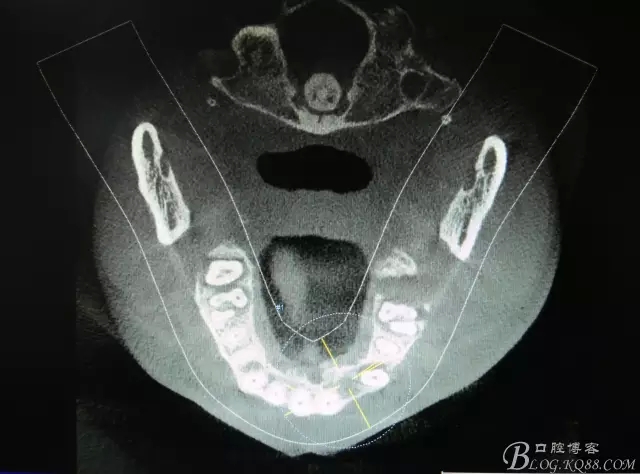

患者、楊xx、男、49歲。主訴:左側(cè)前牙拔除半年,活動(dòng)義齒修復(fù)四個(gè)月,要求種植修復(fù)。??茩z查:21缺失,牙槽粘膜厚度正常。CBCT檢查:高度16mm,寬度7mm.術(shù)前簽知情同意書。

圖2.CBCT的三維成像及縱剖面、水平面影像